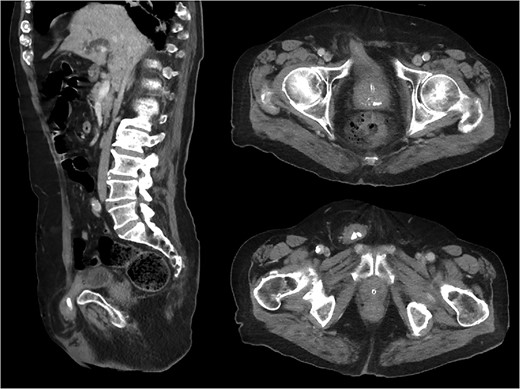

CT abdomen and pelvis was performed to assess whether any bowel was involved in order to determine the urgency of surgical intervention. The CT showed a right-sided inguinal hernia containing a portion of the urinary bladder, with bladder calculi entrapped within the hernia (Fig. 1).

Sagittal and axial CT images demonstrating right-sided inguinal bladder hernia containing radio-opaque bladder calculi.